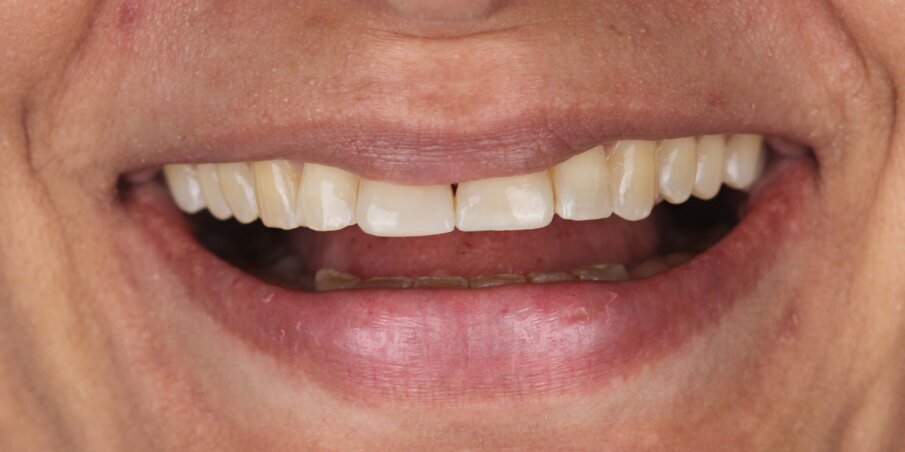

Smile analysis reveals the presence of a reverse smile line giving the patient a slightly senile appearance (Fig 4).

Fig 4: Initial smile